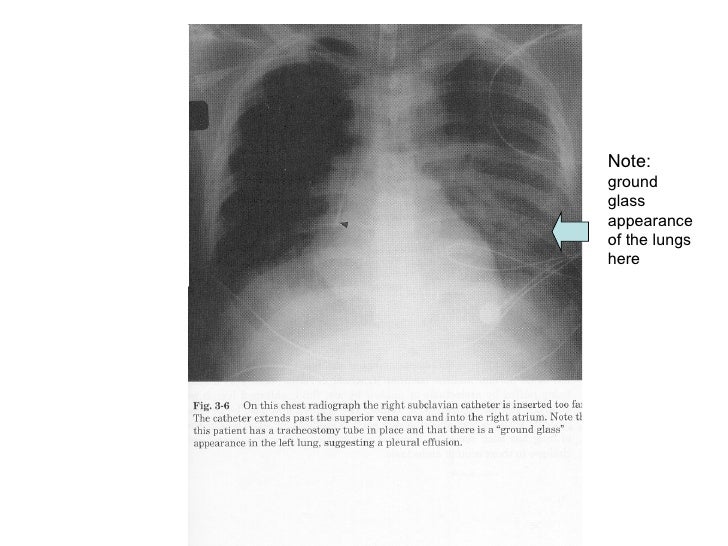

From www.slideshare.net

Chest X Ray Interpretation X Ray Ground Glass Appearance Ground glass opacity (ggo) refers to the hazy gray areas that can show up in ct scans of the lungs. In fact, ggo is a. The finding can be one small spot all the way to involve the lungs throughout. Ground glass looks hazy or cloudy compared to the normal dark lung. These areas show increased density inside the lungs. X Ray Ground Glass Appearance.